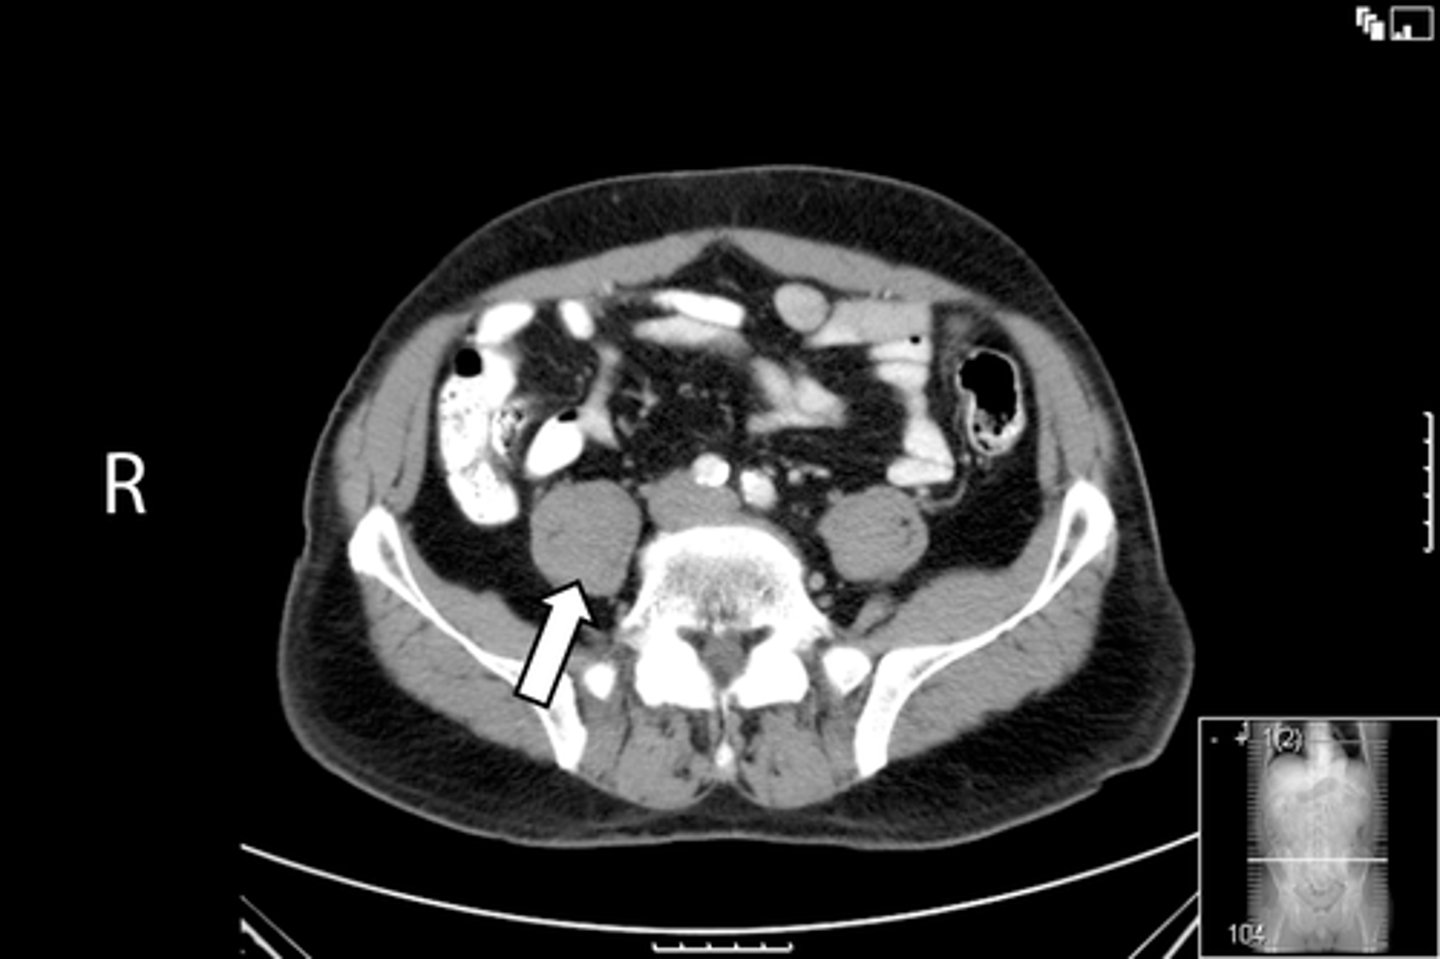

<p>What is indicated in the image?</p>

9

New cards

Ischial tuberosity

What is indicated in the image?

10

Nonfused greater trochanter

11